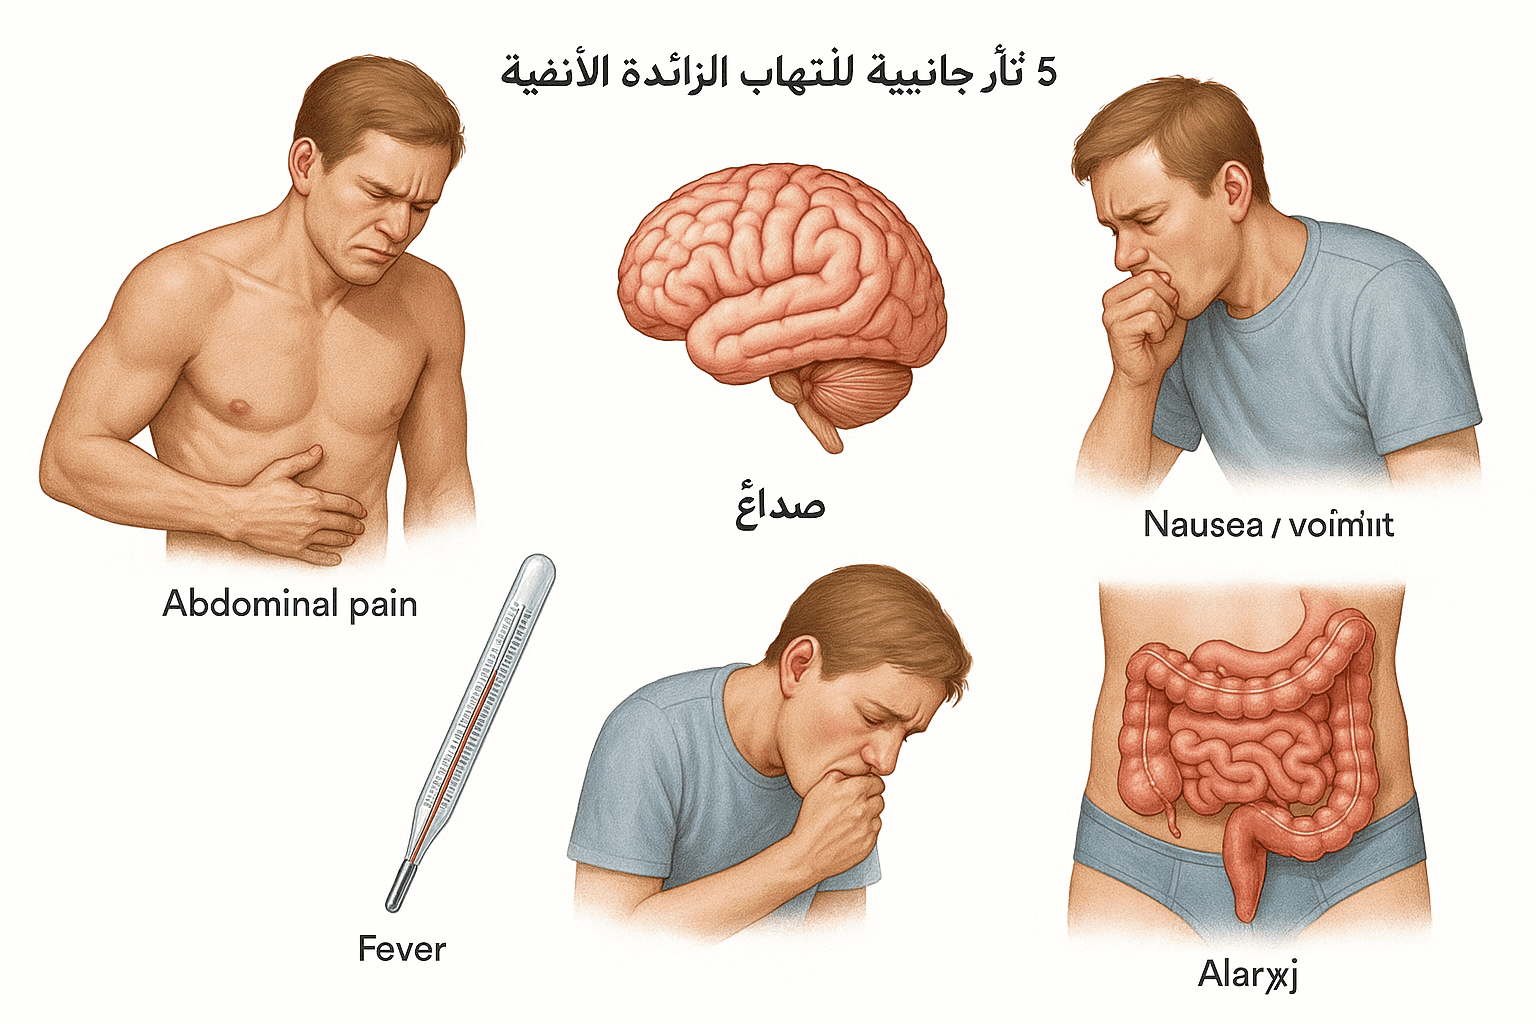

نغطي كل التخصصات الطبية

استیعاب کافة الحالات الطبیة لشمولیة التخصصات

مقالات طبية من مساهمات الأطباء